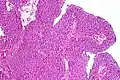

Immunohistochemistry for p53 can help distinguish a PUNLMP from a low grade urothelial carcinoma. Overexpression is seen in 75% of low-grade urothelial carcinomas and only 10% of PUNLMP.[12][13]

12. ^ Image is taken from following source, with some modification by Mikael Häggström, MD:

- Schallenberg S, Plage H, Hofbauer S, Furlano K, Weinberger S, Bruch PG; et al. (2023). "Altered p53/p16 expression is linked to urothelial carcinoma progression but largely unrelated to prognosis in muscle-invasive tumors". Acta Oncol. 62 (12): 1–10. doi:10.1080/0284186X.2023.2277344. PMID 37938166.{{cite journal}}: CS1 maint: multiple names: authors list (link)

13. ^ Source for role in distinguishing PUNLMP from low-grade carcinoma:

- Kalantari MR, Ahmadnia H (2007). "P53 overexpression in bladder urothelial neoplasms: new aspect of World Health Organization/International Society of Urological Pathology classification". Urol J. 4 (4): 230–3. PMID 18270948.